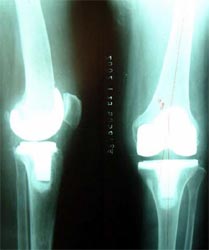

病例一、患者男性,76岁,双膝疼痛10年,屈伸受限,下蹲困难。线片显示双膝骨关节炎改变,关节间隙已经消失。严重膝内翻畸形。

为患者行一期双膝置换术,X线片显示假体位置好,下肢力线恢复。